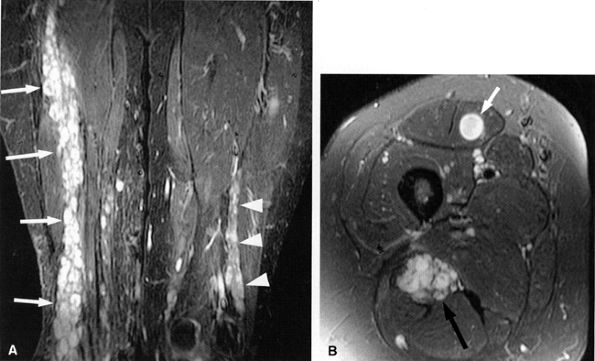

FIGURE 6.10 ● Sciatic neuropathy associated with rhabdomyolysis. Increased signal in the sciatic nerve (arrows) is shown on this coronal fluid-sensitive fat-suppressed image. Note the increased signal in multiple muscles.

FIGURE 6.14 ● Plexiform neurofibromatosis. (A) Coronal T2-weighted fat-suppressed image depicting fusiform enlargement and increased signal of the right (arrows) and left (arrowheads) sciatic nerves. (B) Axial T2-weighted fat-suppressed image demonstrating the “bag of worms” appearance of the right sciatic nerve (black arrow). Note an intramuscular neurofibroma in the rectus femoris muscle (white arrow).